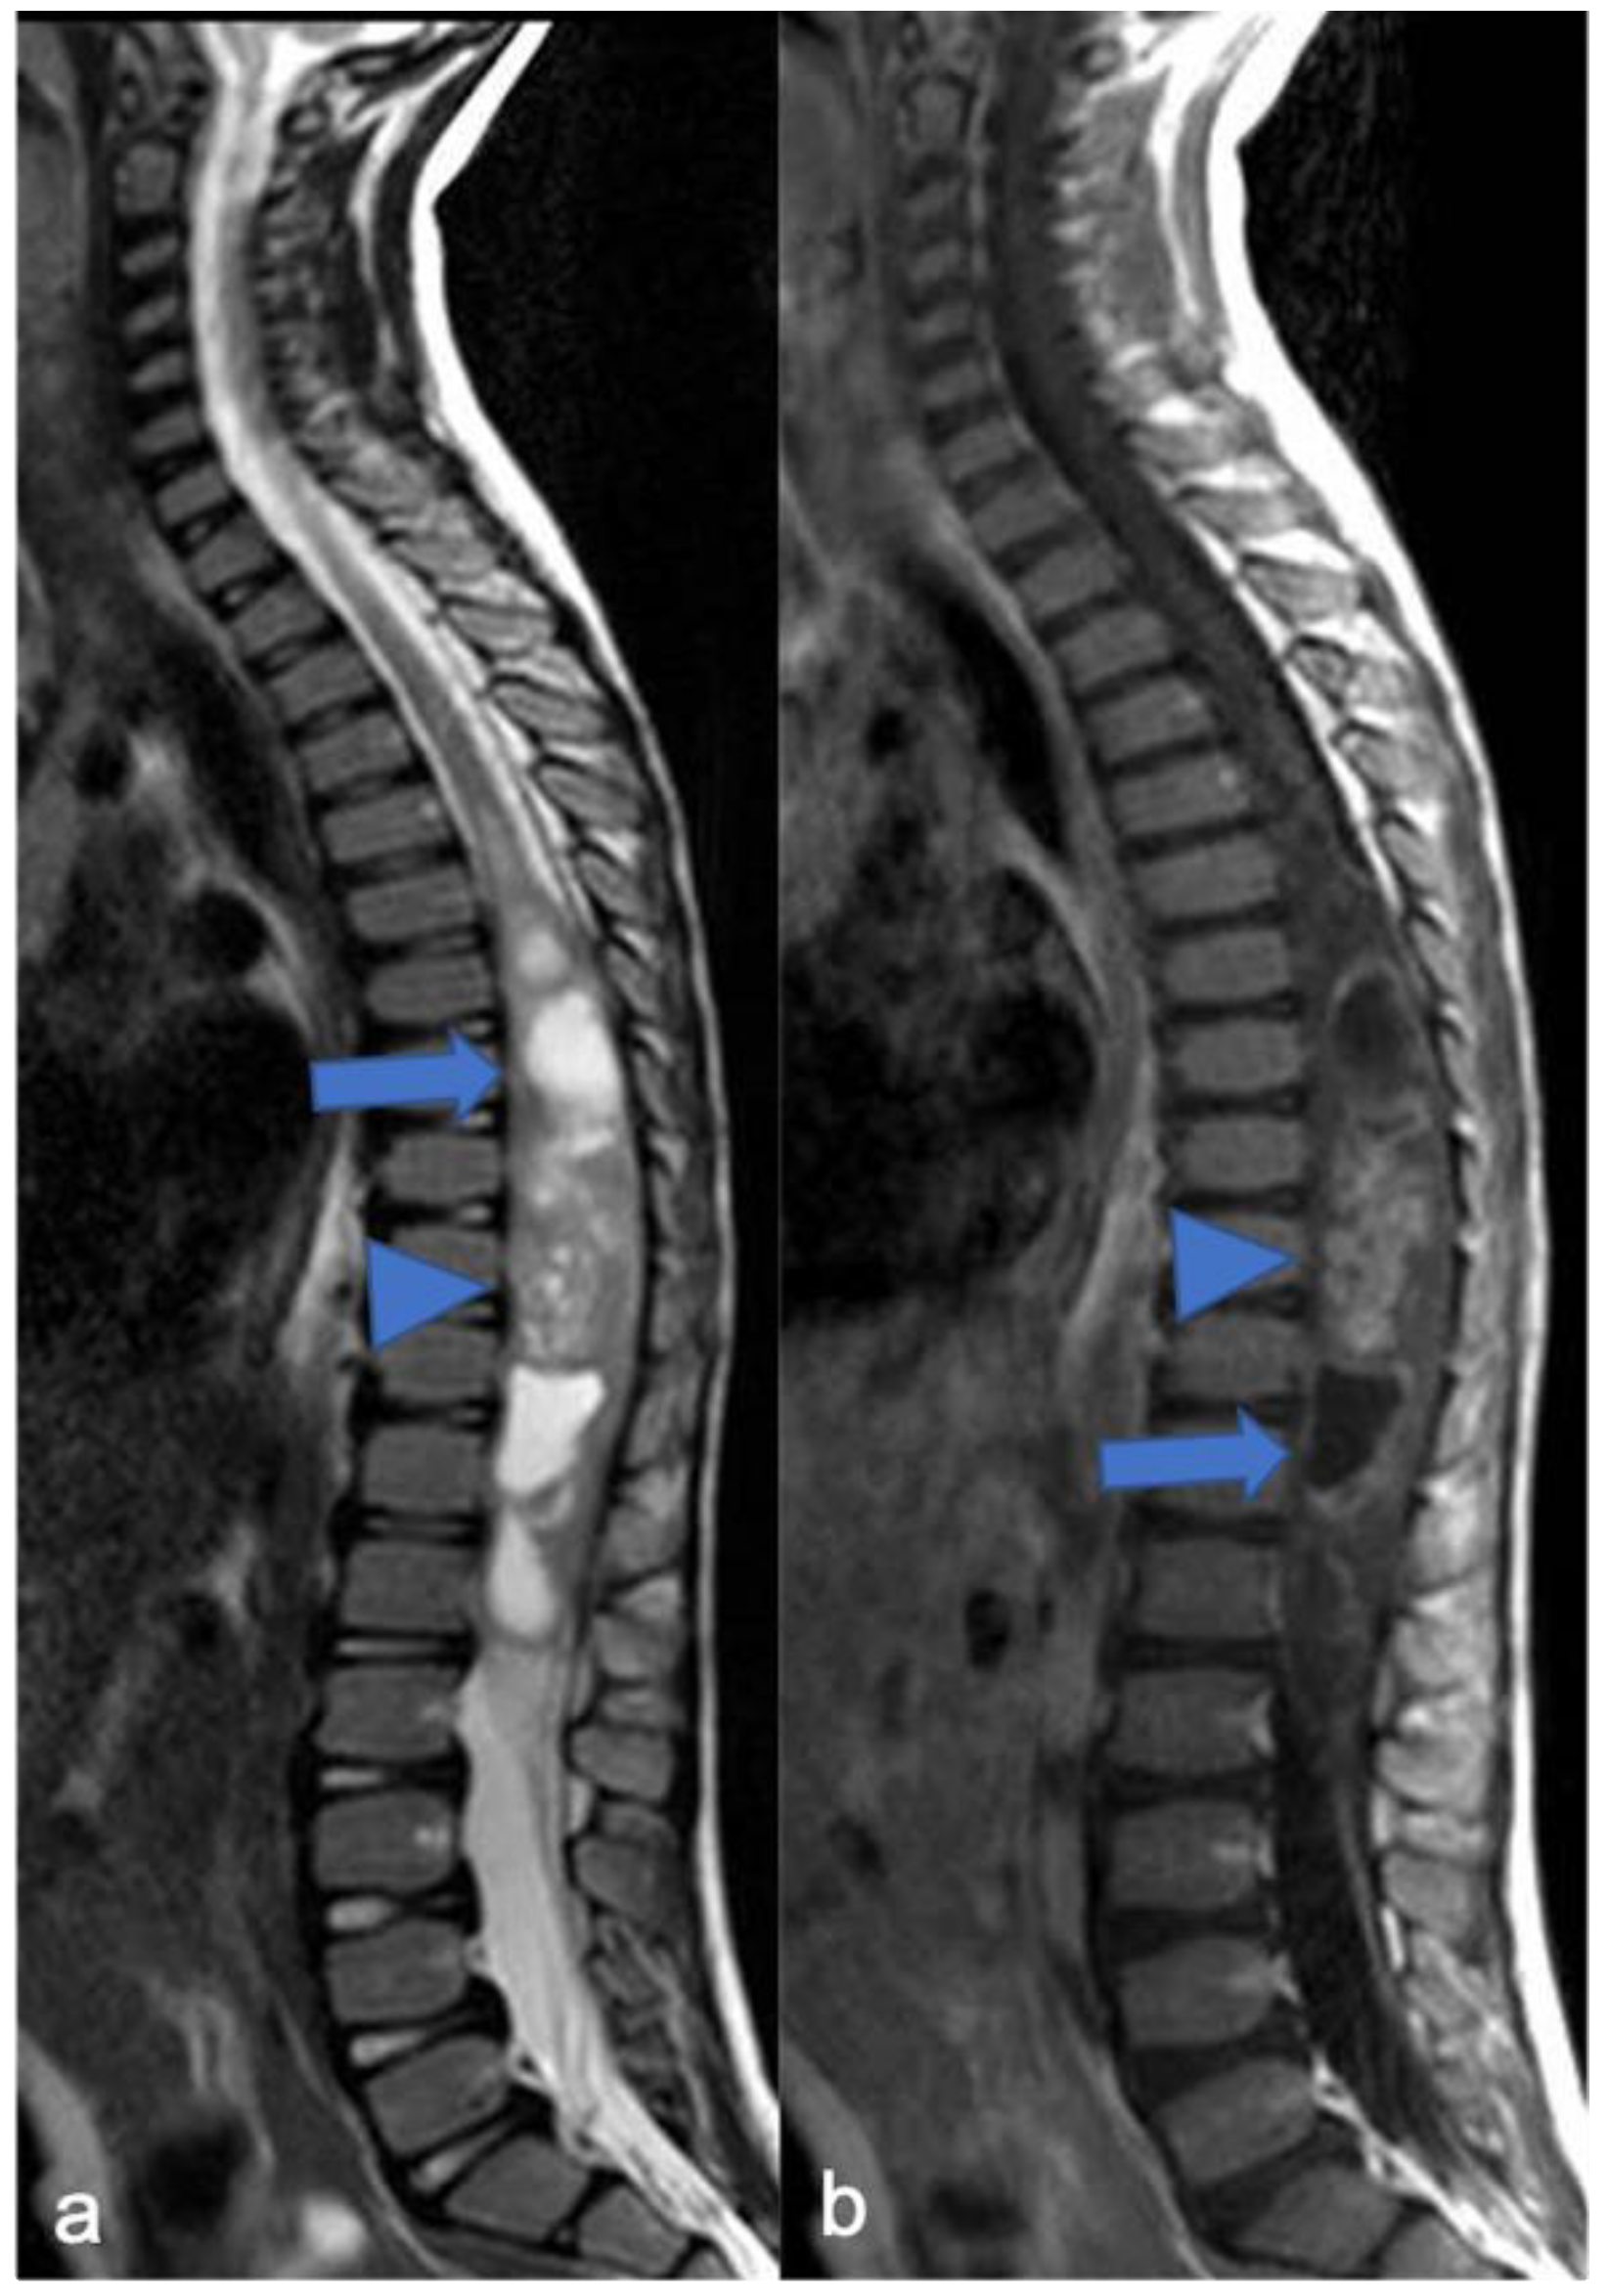

Figure 6.

Diffuse leptomeningeal glioneuronal tumor in a four-year-old child. Sagittal T2-weighted (a) and post-contrast T1-weighted (b) images show multiple spinal and subtentorial cystic-like leptomeningeal nodular lesions (arrows) with diffuse sheets enhancement (arrowheads).